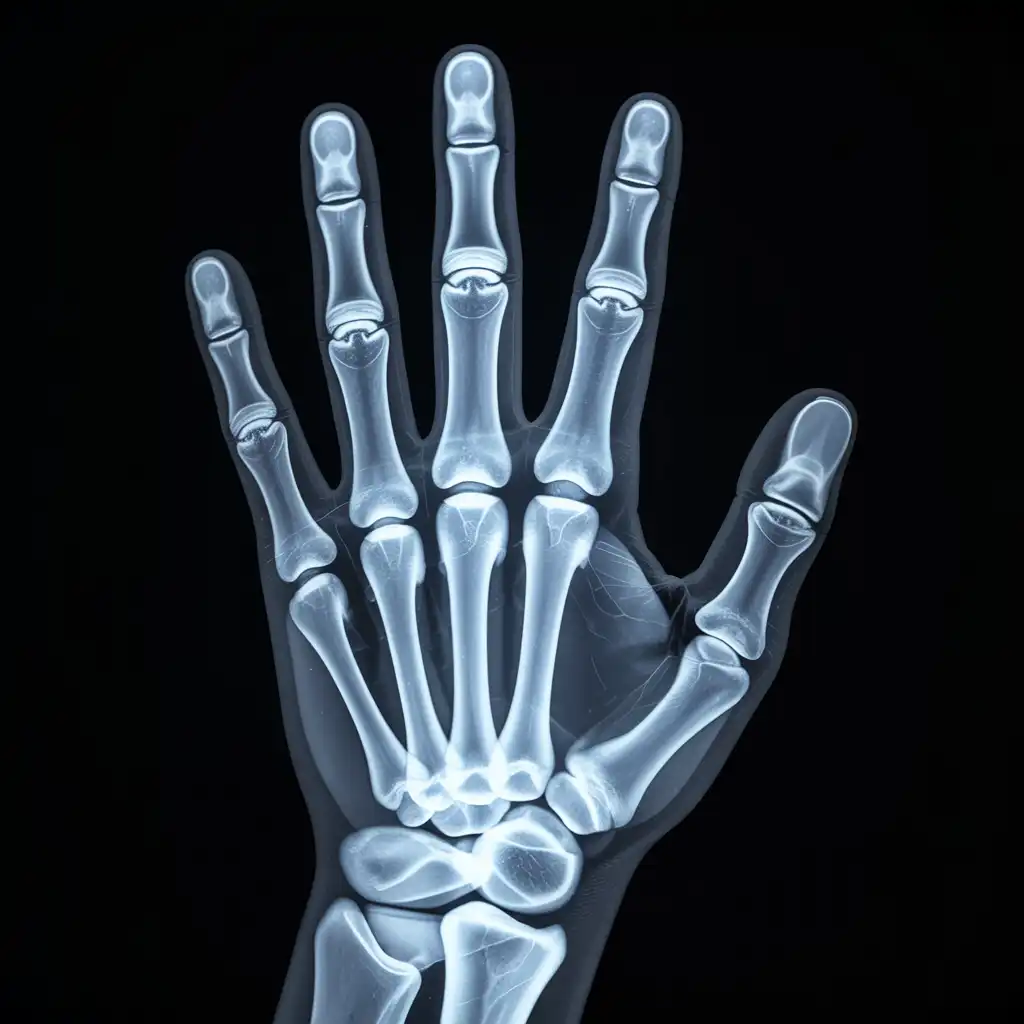

Una radiografia a domicilio è un esame radiologico eseguito da un tecnico specializzato che viene a casa tua con apparecchiature digitali portatili. L’esame si svolge sul posto, senza spostare il paziente e con la stessa qualità di una struttura ospedaliera.

Dopo l’acquisizione delle immagini, queste vengono inviate al medico radiologo che referta rapidamente e ti invia tutto in formato digitale. Un servizio comodo, sicuro e ideale per chi ha difficoltà negli spostamenti.